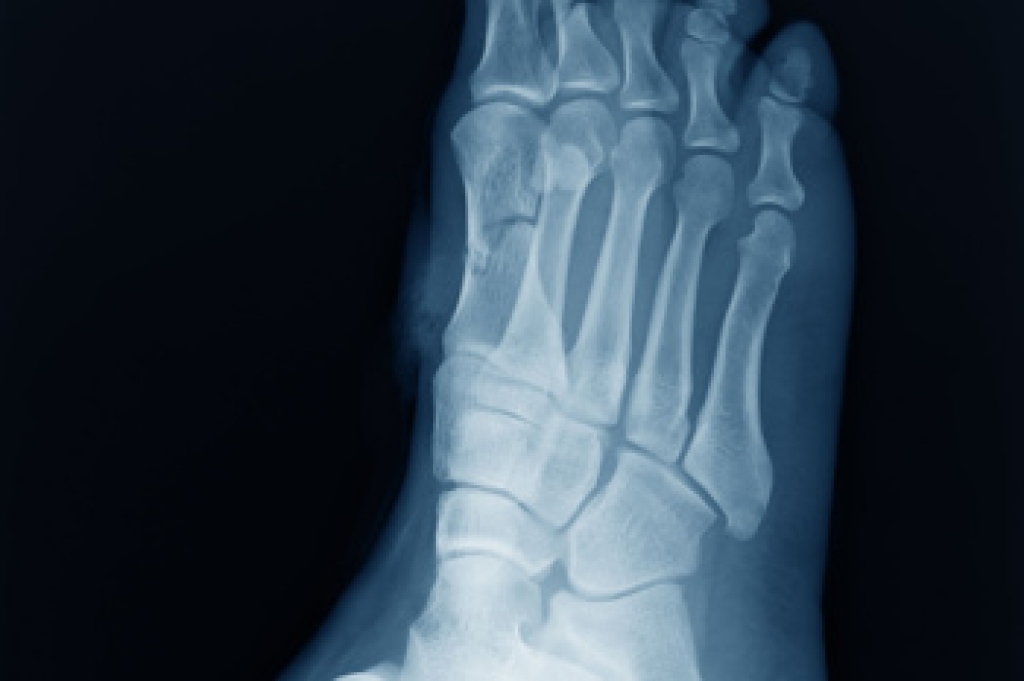

Gout is a form of arthritis that is characterized by sudden, severe attacks of pain, redness, and tenderness in the joints. The condition usually affects the joint at the base of the big toe. A gout attack can occur at any random time, such as the middle of the night while you are asleep.

- Intense Joint Pain - Usually around the large joint of your big toe, and it most severe within the first four to twelve hours

- Inflammation and Redness -Affected joints may become swollen, tender, warm and red